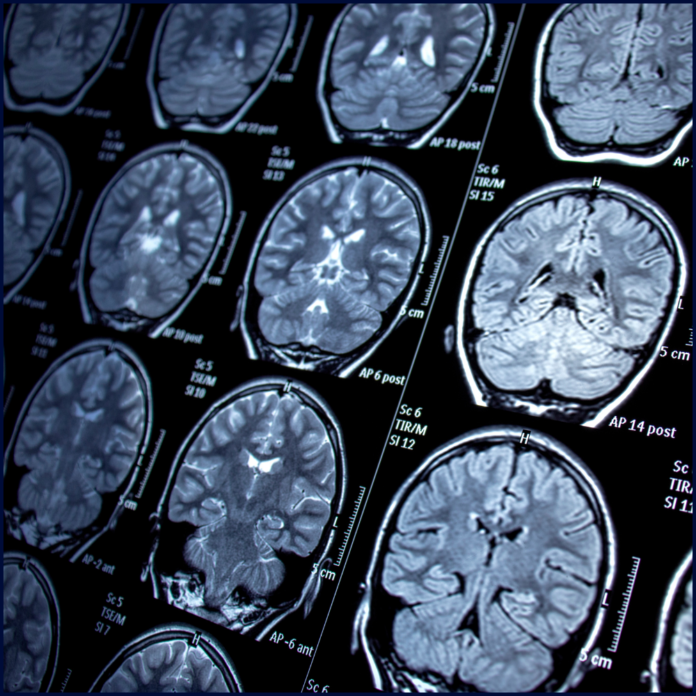

The study will be conducted at the University of Utah, utilizing the facilities of the Huntsman Mental Health Institute (HMHI) and the School of Medicine. It investigates the role of interoceptive awareness in the therapeutic effects of Swedish Massage Therapy (SMT) compared to Light Touch (LT) for Generalized Anxiety Disorder (GAD). It examines whether changes in interoceptive awareness mediate or moderate the relationship between touch interventions and reductions in GAD symptoms, and how these changes relate to neuroimaging and autonomic data. The project leverages two ongoing randomized, single-masked clinical trials comparing SMT and LT in individuals with GAD and non-psychiatric controls.